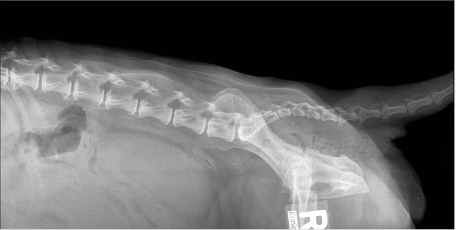

Anamnèse : Elkhound norvégien, femelle, 16 ans, présentée pour faiblesse et ataxie des membres pelviens.

Qu’en pensez-vous?

Spondylose, mais n’explique pas les signes cliniques